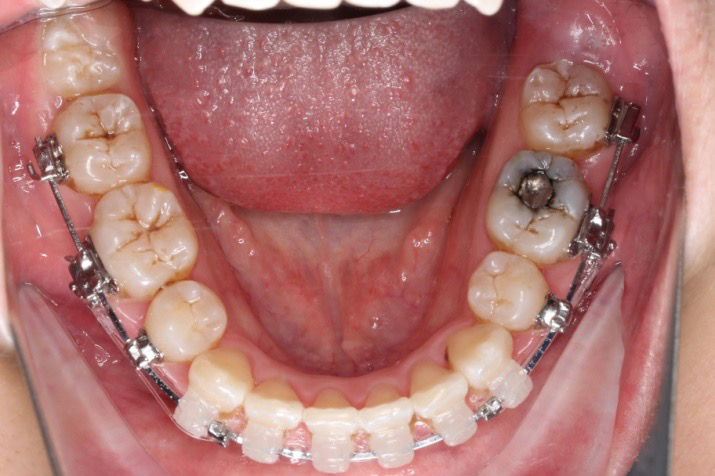

2018.11.14  术后磨牙尖牙I类关系,中线齐,覆合,覆盖正常

牙根基本平行,未见牙根吸收

10 M after Post-Tx

10 M after Post-Tr

2019.08.06  术后  10个月复查